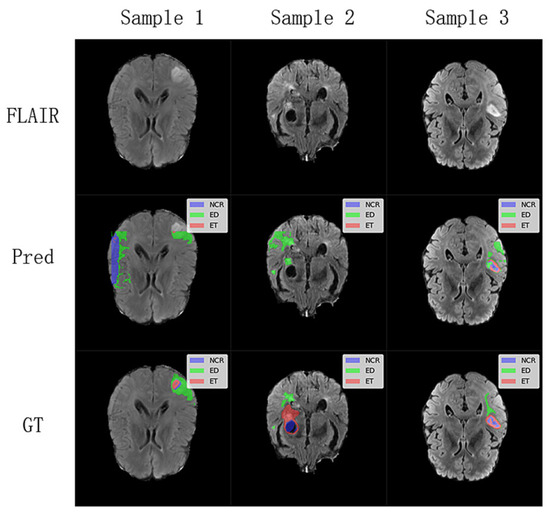

To further understand the limitations of our proposed model, we investigated challenging cases where segmentation performance was suboptimal, as illustrated in Figure 6. These cases, identified through an analysis of outliers in our test set quantitative metrics, highlight specific scenarios where the model struggles. These challenging cases suggest that while our lightweight model performs well on average, its performance can be compromised in images with very low contrast between tumor and healthy tissue, or for particularly heterogeneous or small tumor sub-regions. The model’s efficiency, achieved through a reduced parameter count, might lead to a diminished capacity to learn highly complex and subtle feature variations present in these difficult instances. Future work could focus on targeted data augmentation for such low-contrast scenarios or a more sophisticated feature enhancement module to improve robustness in these specific failure modes.

Figure 6. Analysis of challenging segmentation cases from the BraTS2020 and FeTS2022 testing dataset. The first row displays the FLAIR sequence (middle slice) of three distinct subjects where our model encountered difficulties. The Pred row shows the corresponding segmentation predictions from the WIAF model, and the GT row presents the ground truth labels.